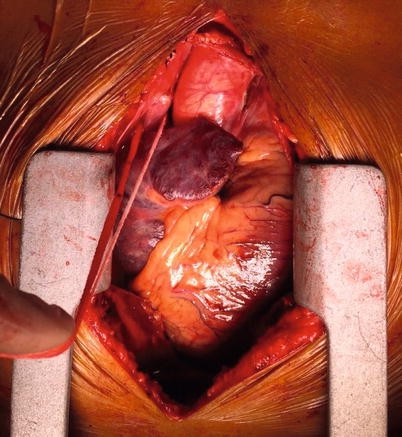

Fig. 37.6

A looped innominate (or brachiocephalic) vein being pointed at by a surgical diathermy